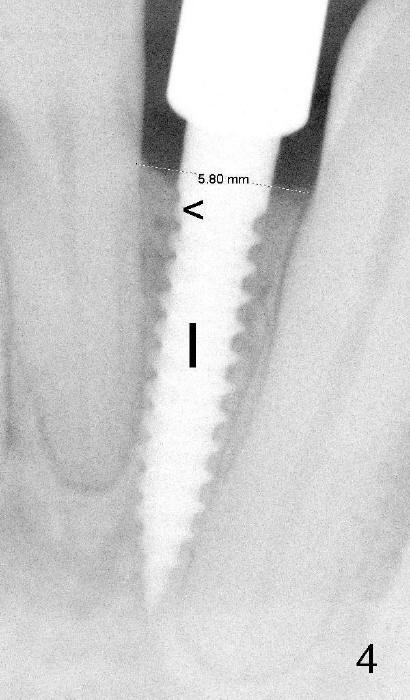

Fig.4: A 3x17 mm one piece implant is placed (I). The 1st thread is subcrestal (<). 术后邻牙轻度叩痛